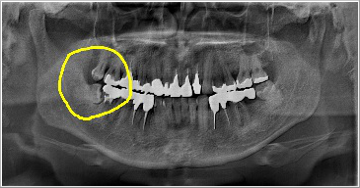

これは横向きに出てきた親知らずとその前の歯との間に食べ物が詰まり、取れなくなった為に奥の方まで炎症が広がり、結果的に前の歯を抜かなければならなくなった症例です。 この患者さんは「右下奥歯が動き出し、痛くて噛めなくなりました」といって来院されました。

また、一見それほど大きな虫歯ではない様に見える歯でも、少し顔を出した親知らずの為に抜かなければならぬ程の大きな虫歯になっている事もあるのです。